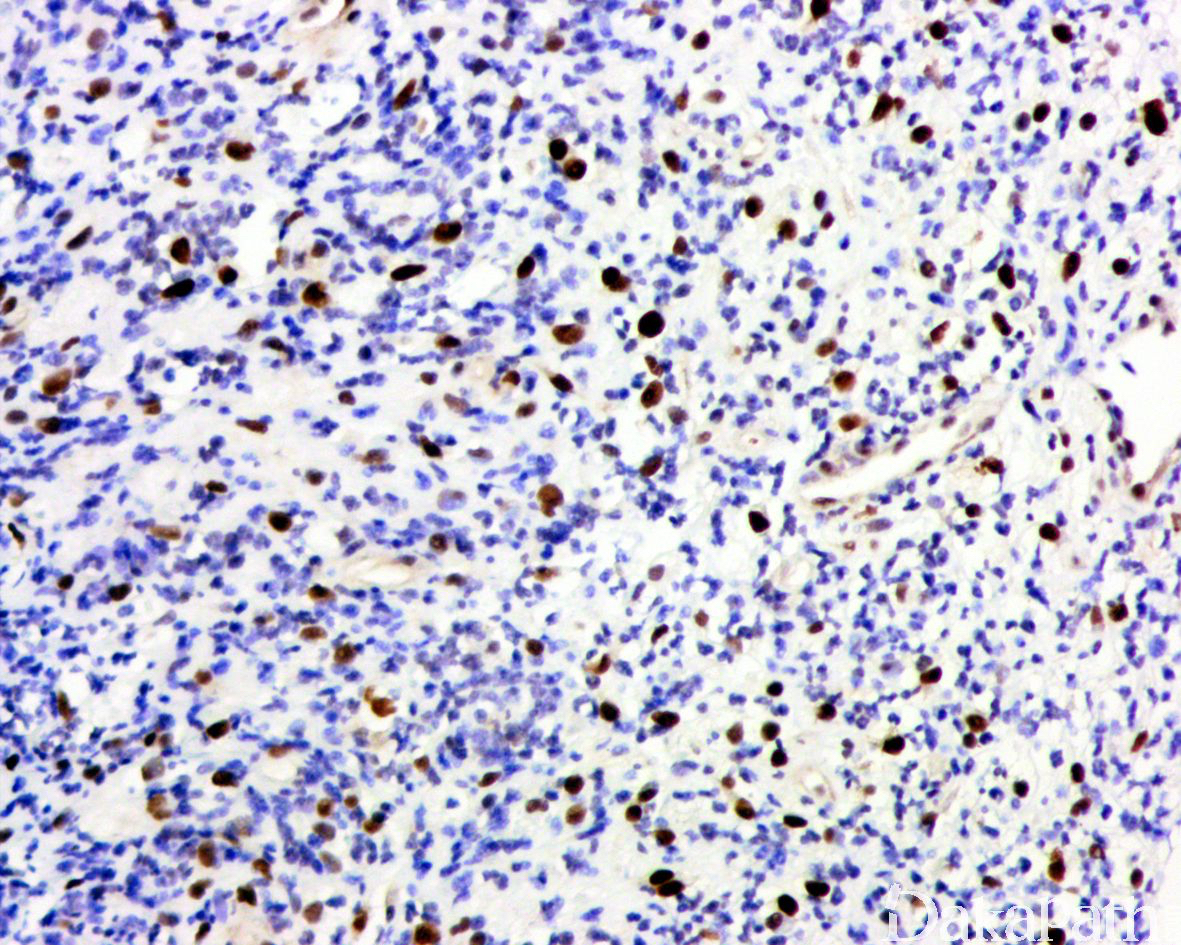

免疫组织化学染色,绝大多数的 DDLPS 弥漫强表达 p16 蛋白(核和质表达),是诊断 DDLPS 最敏感的标志物,但缺乏特异性,许多与之形态学相似的肿瘤,特别是高级别肿瘤(如平滑肌肉瘤和肉瘤样癌等)亦可弥漫表达 p16。由于 DDLPS 一致性的存在 12q14-15 区域的扩增和过表达,而 MDM2 蛋白和 CDK4 蛋白的强表达与相应的基因扩增存在高度的一致性,因此免疫组织化学染色 MDM2 和 CDK4 的共表达(均为弥漫核表达)对于诊断 DDLPS 具有较大的帮助。在与 ALT/WDLPS 之外的其他类型的脂肪源性肿瘤的鉴别诊断中,联合应用 p16. MDM2 和 CDK4 对于诊断 DDLPS 具有高度的敏感性和特异性,93%的 DDLPS 表达上述 3 个标志物中的至少 2 个,72%表达全部 3 个标志物。但在 DDLPS 与非脂肪源性的肿瘤鉴别诊断时,上述 3 个标志物的特异性则明显不够;此时,应用荧光原位杂交(FISH)检测 MDM2 基因的扩增对于诊断 DDLPS(在适当的组织学背景下)具有高度的特异性和敏感性,尤其是在小活检标本、未见典型的 ALT/WDLPS 成分、低级别去分化和少见特殊类型的 DDLPS 诊断时更是如此。MDM2 基因的扩增目前普遍认为是诊断 ALT/WDLPS 和 DDLPS 的金标准,需要指出的是,MDM2 基因扩增并非 ALT/WDLPS 和 DDLPS 所特有,其他常见存在 MDM2 基因扩增的肿瘤还包括低级别中央型骨肉瘤、骨旁骨肉瘤以及原发的心脏内膜肉瘤等。约半数左右的 DDLPS 可局灶或弥漫表达 CD34,去分化成分一般不表达 S100 蛋白,伴有肌纤维母细胞分化者可表达 SMA 和 MSA 或结蛋白[23],伴有横纹肌和平滑肌分化者可分别表达 MyoD1 和 H-caldesmon,具有脑膜上皮瘤样漩涡特征的 DDLPS 可表达 SMA 和 Claudin-1 提示其肌纤维母细胞或神经束膜分化的特征。新近发现,约 6%的 DDLPS 可见 H3k27me3 的表达缺失易与恶性外周神经鞘膜瘤(MPNST)混淆,约 11%的 DDLPS 可见 STAT6 基因扩增从而局灶或弥漫表达 STAT6 易误诊为孤立性纤维性肿瘤(SFT)。